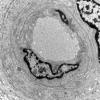

PERIPHERAL NEUROPATHY

11 VASCULITIS - VASCULOPATHY

2 Vasculopathy (7)